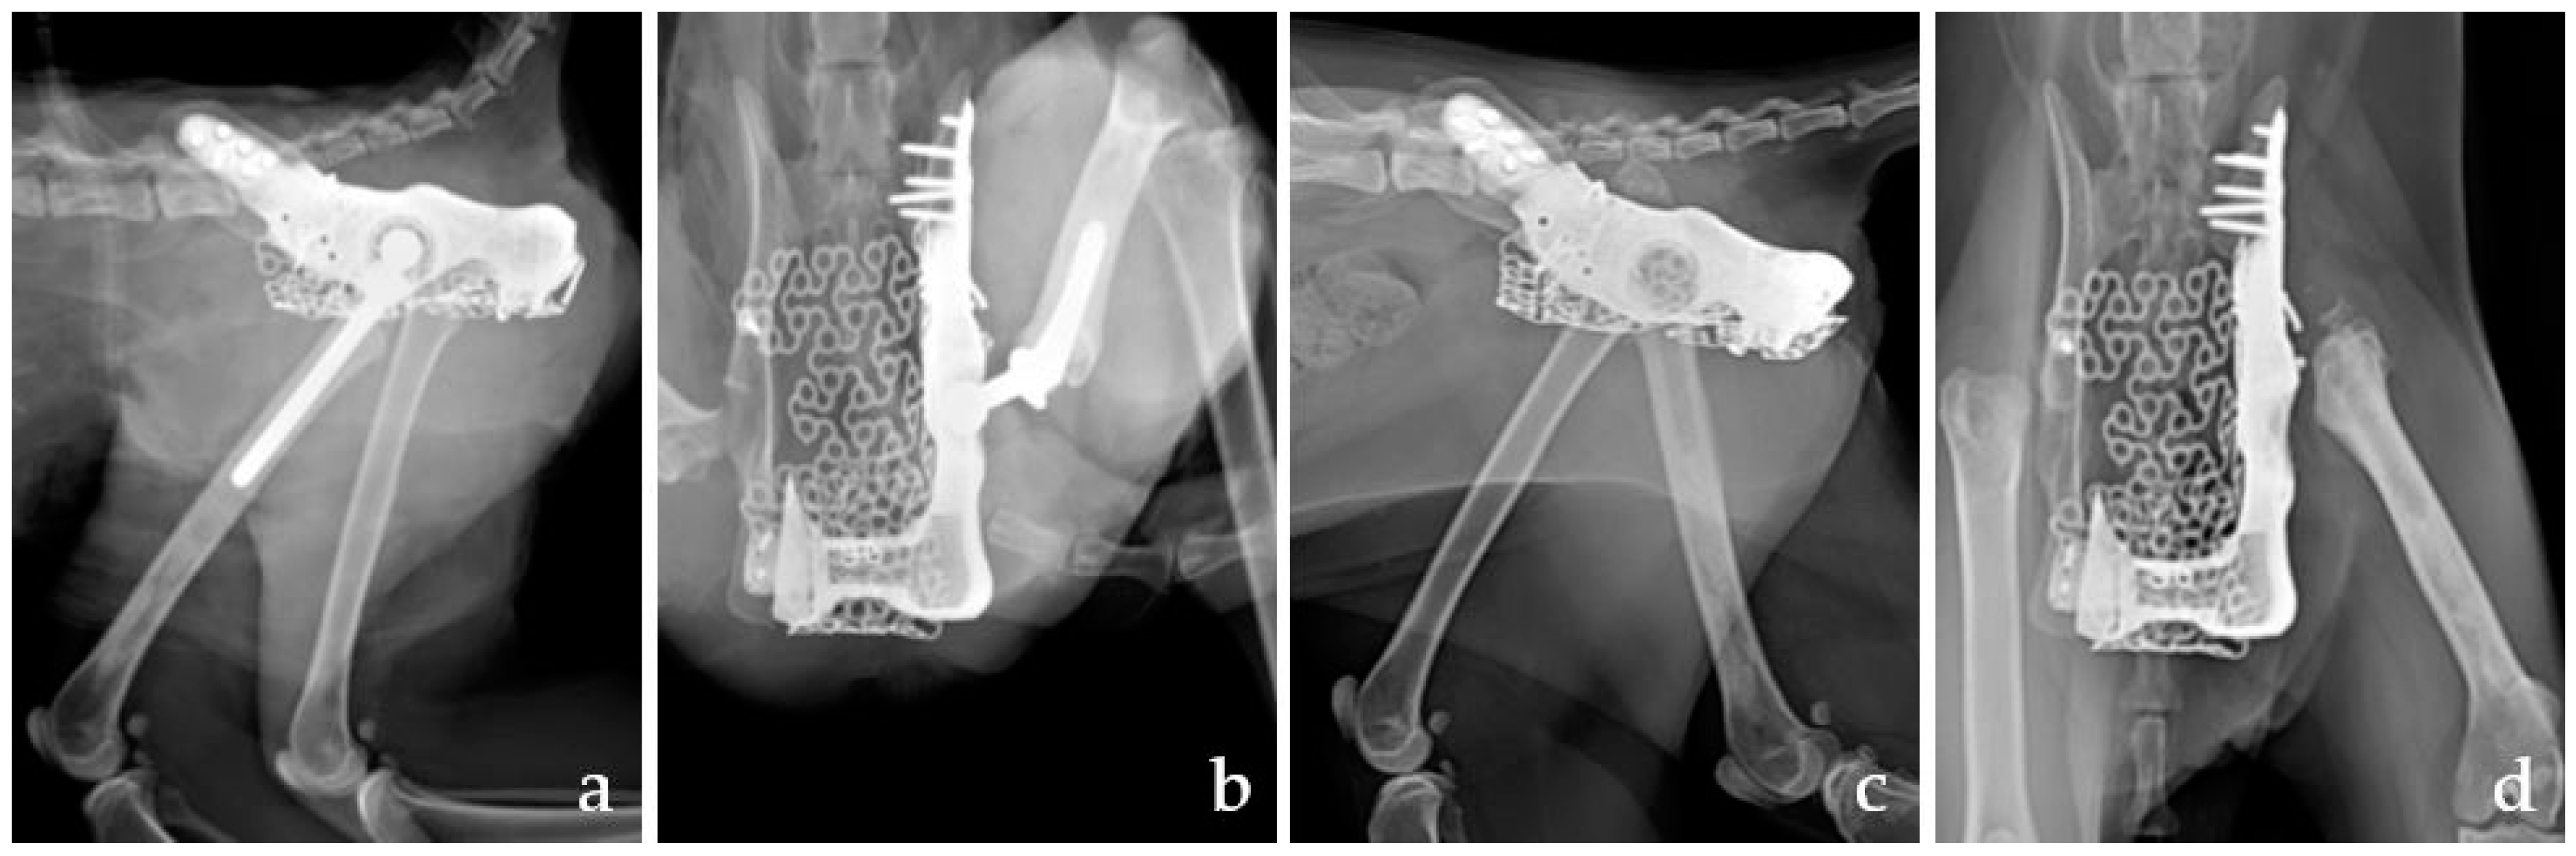

2.4. Surgical Technique

2.5. Outcomes, Complication, and Follow-Up